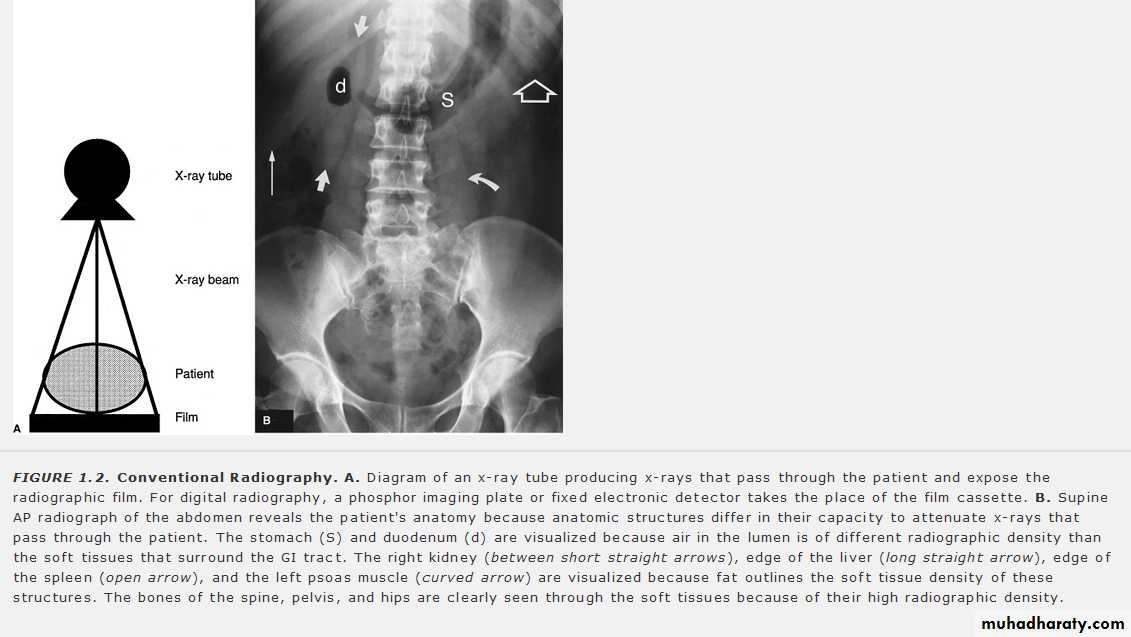

X-rays are generated in an X-ray tube, which consists of a vacuum tube with a cathode (tugestone fillament ) and an anode (tungestone target) . The x-ray beam is produced by bombarding a tungsten target with an electron beam within an x-ray tube .

The X-ray image is formed by the transmitted photons. those that are absorbed or scattered represent attenuation by matter .

An understanding of how the properties of X-ray and the materials through which they travel affect the relative amount of attenuation and transmission gives an understanding of how the X-ray image is formed.

According to x- ray attenuation in the tissues ( x – ray penetration) ,the radiographic appearace can be graded into :

Tranceradiant as gases

Radiolucent or trancelucent as in fatty tissue

Mild radio radio-opague as fluid , muscle ..

Moderate radio-opague as bones and calcifications

Dense radio-opague as metals and contrasts

The four basic densities on an x-ray. A lateral view of the forearm shows that the bones are the densest, or white; soft tissue is gray; fat is somewhat dark; and air is very dark. The abnormality in this case is the fat in the soft tissue of the forearm, which is due to a lipoma .